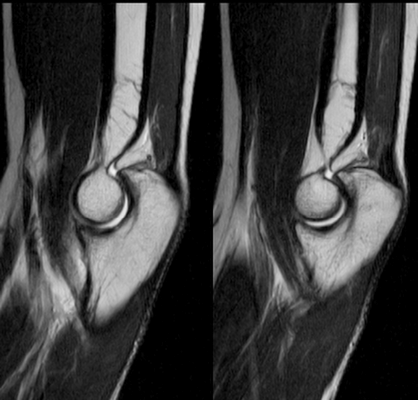

МРТ локтевого сустава в сагиттальной плоскости. Отмечается повышенное скопление свободной синовиальной жидкости в полости локтевого сустава. Синовиальная оболочка умеренно гипертрофирована.